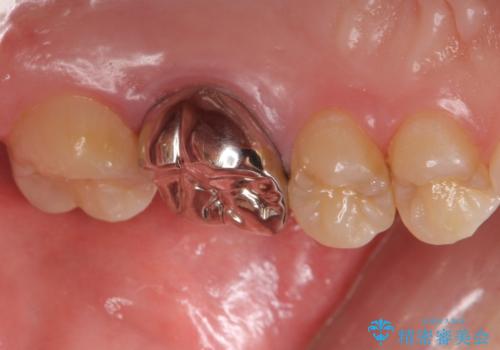

不適合な被せ物 ジルコニアクラウンでの再治療

- 検査の結果被せ物の不適合が見つかった患者様です。

被せ物を除去し、根管治療を進めた後に新しい被せ物を装着していきます。